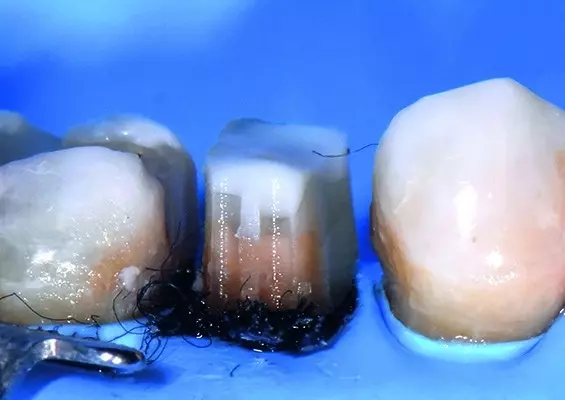

Podczas rewizji optymalny kształt kanału nie zawsze jest oczywisty od samego początku. Na szczęście nowoczesne systemy wsparcia kierują lekarza stomatologa krok po kroku przez anatomię poszczególnych korzeni. W przywoływanym przypadku pokażę, jak zastosowałem nowego, cyfrowego drugiego pilota endodontycznego jako wsparcie w procesie prowadzenia mnie w kierunku wierzchołka.